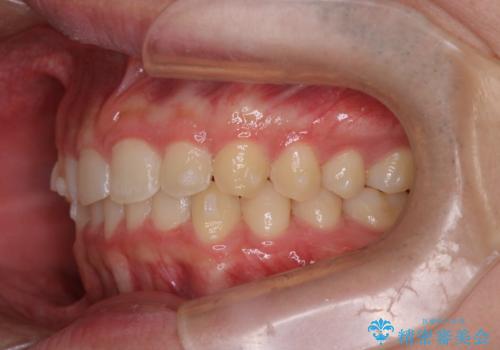

【インビザライン】前歯のガタガタと、前歯の噛み合わせが深いことを治したい。

- 前歯のガタガタと、前歯の噛み合わせが深いことを治したい。との主訴で来院されました。

シミュレーションを用いながら患者様と仕上がりについて相談しインビザラインにて治療を行いました。

仕上げは追加アライナーを数回利用しておこないました。